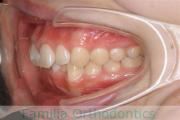

No.22V-185

- 上下顎前突

- 28歳

- 女性

- 抜歯部位

- 上:

- 44

- 下:

- 448

- 主な使用装置:

- FEA 022

- 治療にかかった費用:

- 90万円

口元に力が入ってしまうのを治したいということで来院されました。上の側切歯が小さいのですが、しっかり前歯を後退させたいということで。上下左右から小臼歯を抜歯してマルチブラケット法にて治療を行い、移動後に側切歯の補綴(かぶせ物)処置をしました。

約2年半、30回程度の通院が必要でした。

側切歯が小さい場合、上下の歯のバランスが悪いため、最終段階で人工的な補綴物が必要になります。補綴物には破損や脱離のリスクがあります。